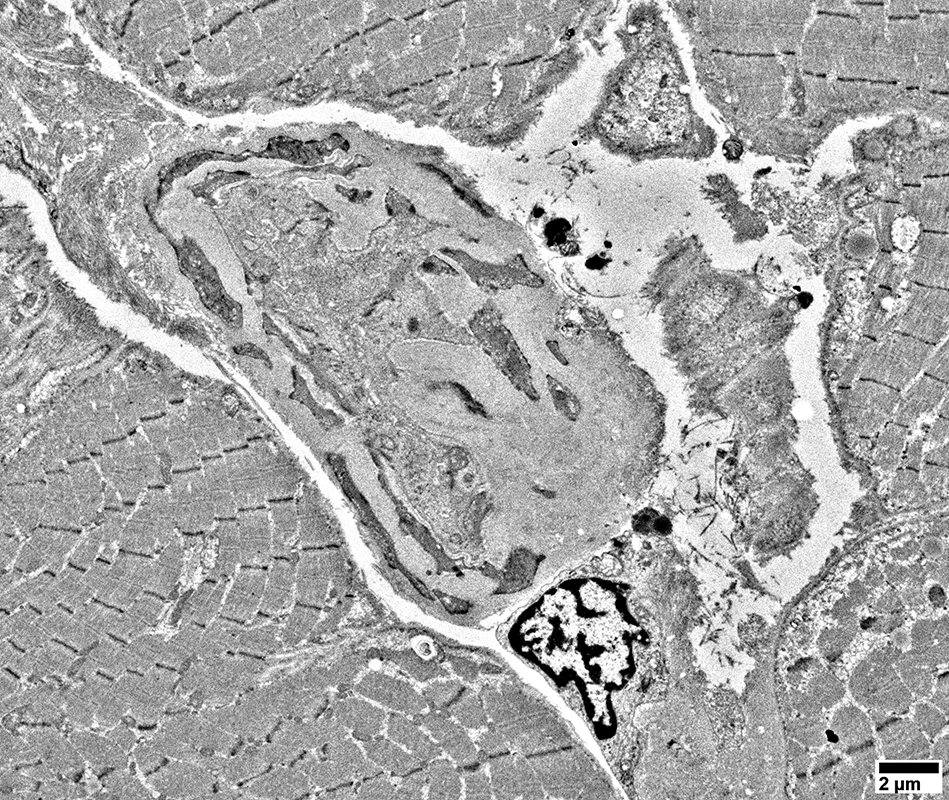

MELAS: 67 year-old female

mtDNA A3243G 66% heteroplasmy

Other disorders: Diabetes; Renal disease, End-stage

Capillaries

Larger vessels

Muscle fibers

Vessel Pathology

Large cells near vessels with

Mitochondrial proliferation & enlargement

Lipid droplets

Large cells near vessels with cytoplasm nearly replaced by

Endomysial vessels with

Large endothelial cells with many vesicles

No lumen

Many smooth muscle cells in wall, some with mitochondrial proliferation (Arrow)

Thick wall

Large endothelial cell with many vesicles

Scattered smooth muscle cells in wall